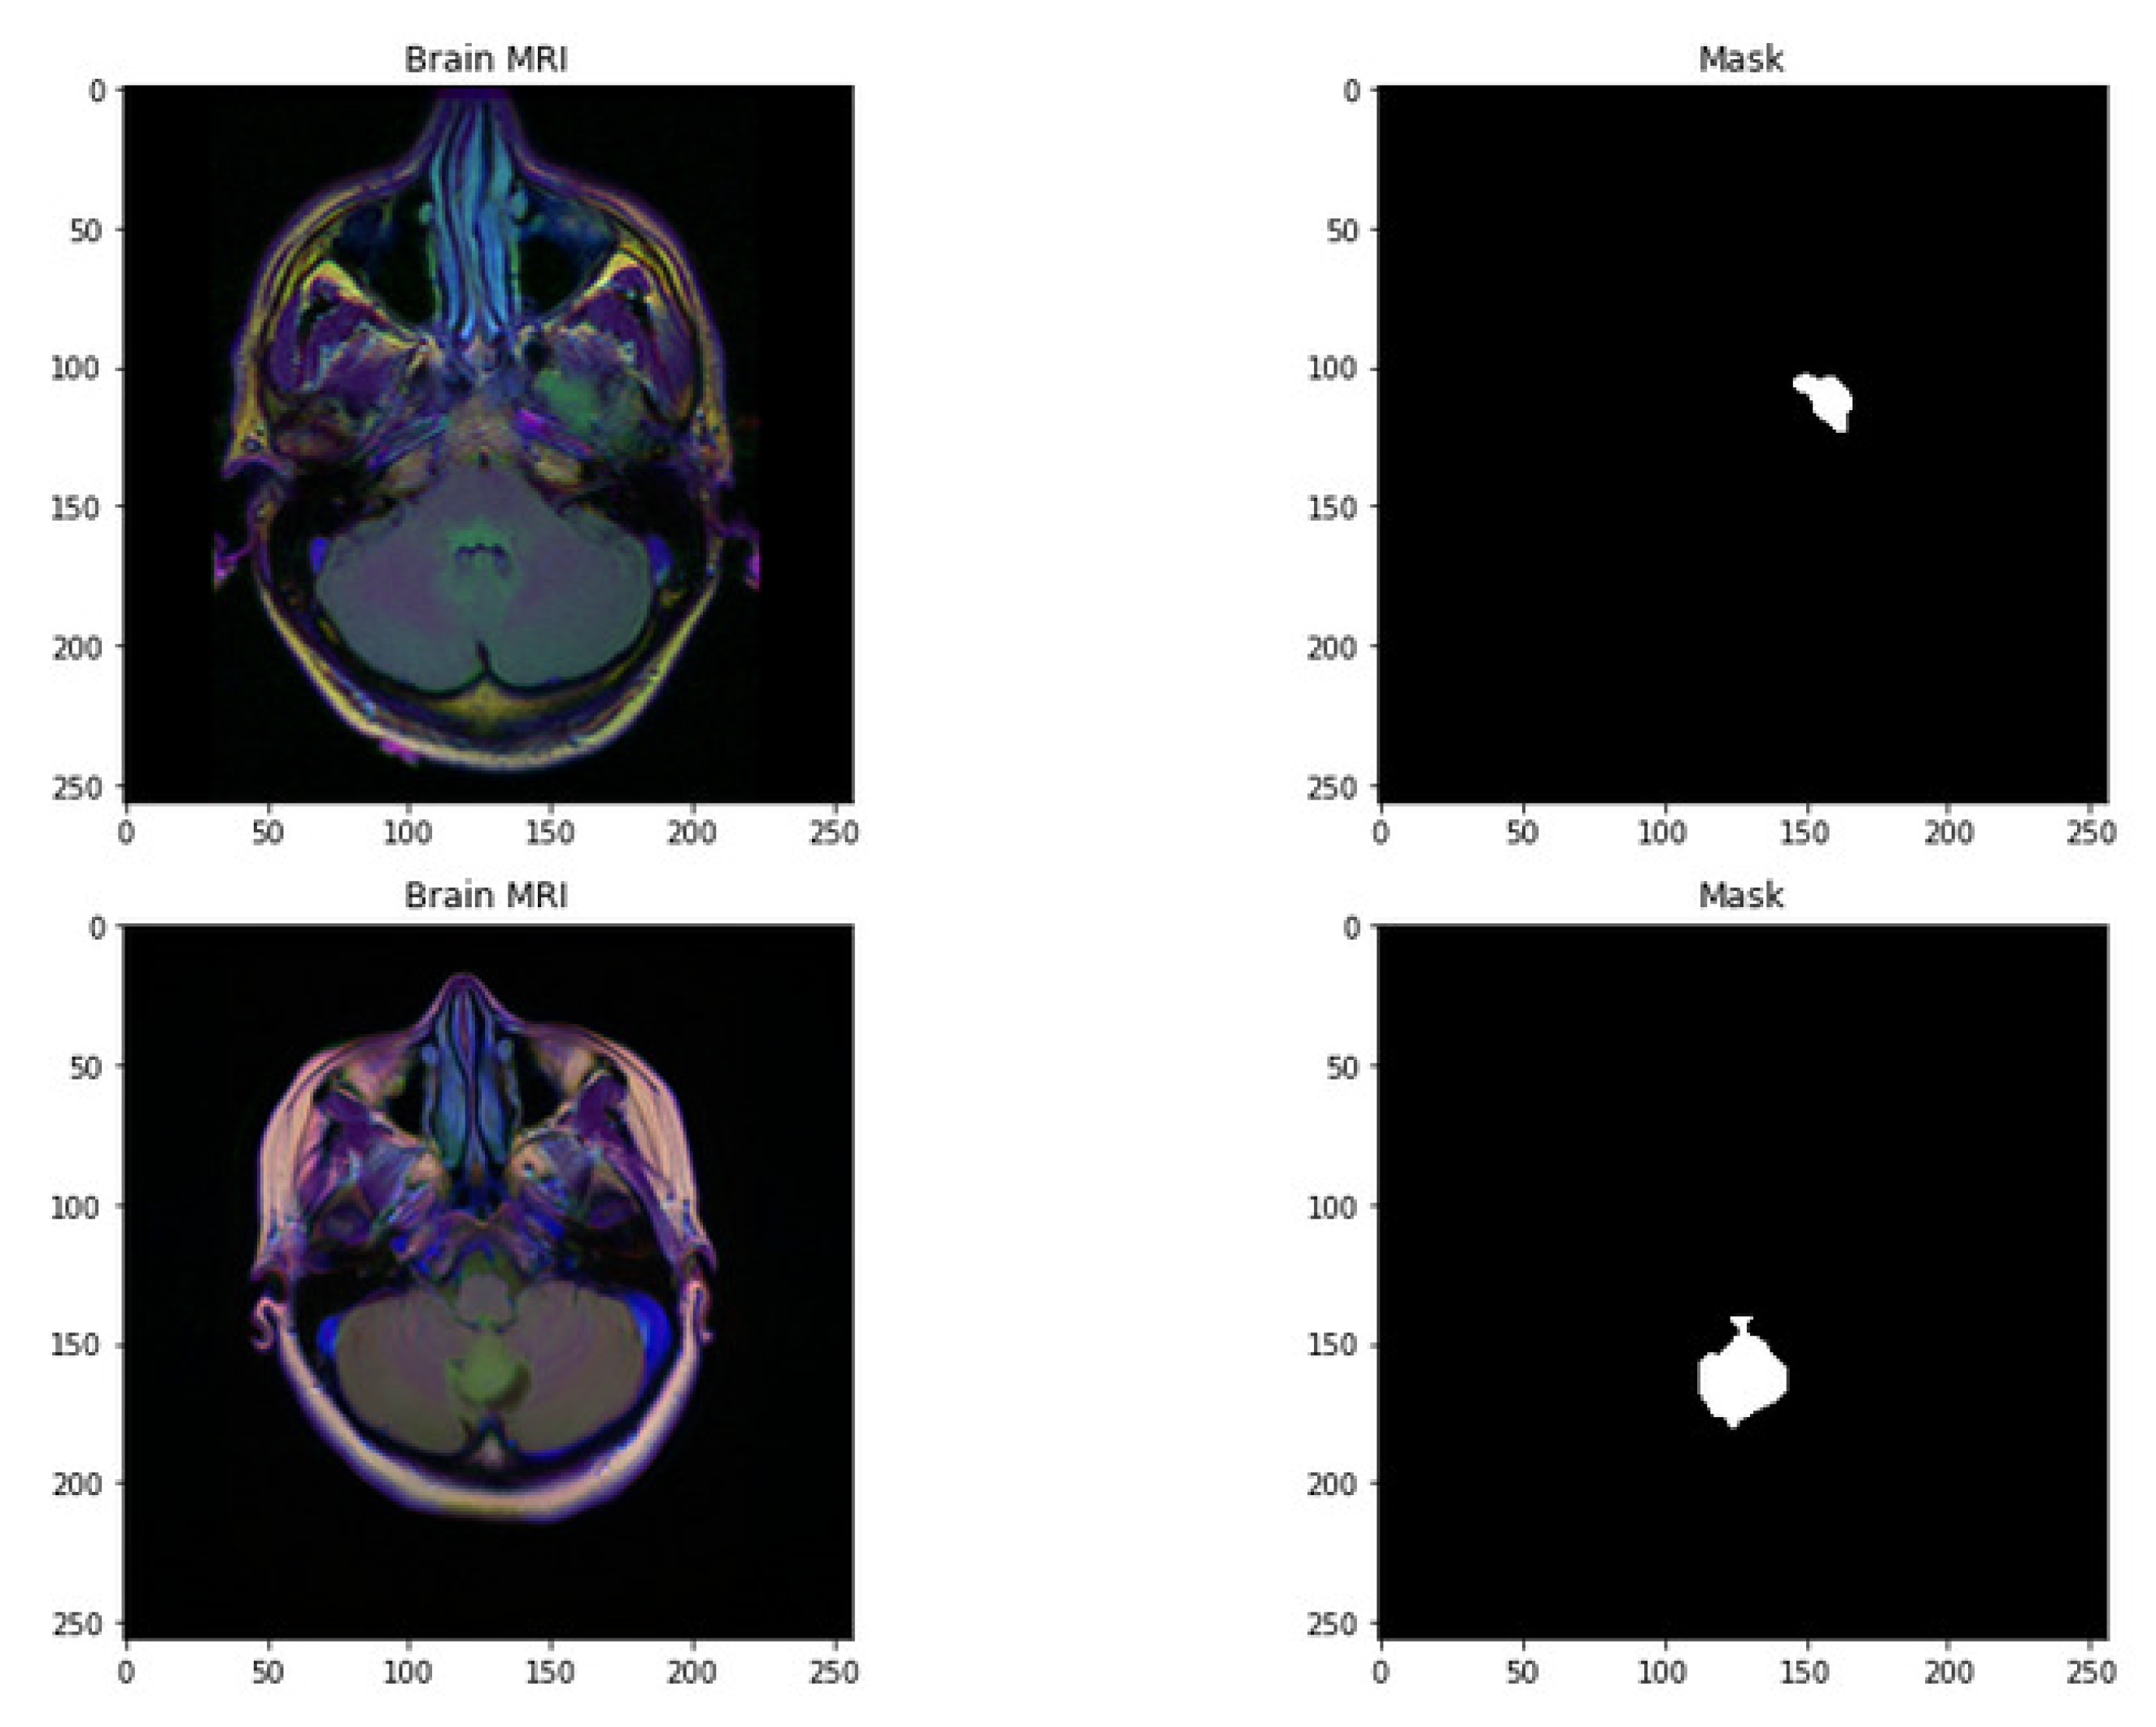

Figure 1.

Random sample images with their corresponding mask.

The dataset used in this work is collected from TCGA (The Cancer Genome Atlas) and TCIA (The Cancer Imaging Archive) [35,36]. The number of identified patients from a lower grade of malignant tumors of the nervous system of TCGA was 120. Individuals had preoperative imaging data, at least one containing an inversion recovery process with fluid attenuation. Ten patients were excluded from this dataset as they required informed consent regarding the available genomic constellation information. The final group that remained in this dataset consisted of the remaining 110 patients. A detailed list of patients has been provided in Online Resource 1. The remaining patients were divided into 22 separate, non-overlapping clusters. Each cluster contains five patients. The process was completed for the evaluation with a cross-validation technique. The imaging dataset used in our research work was captured from the Imaging Archive. Sample images are shown in Figure 1. This dataset consists of the patients’ images related to TCGA and is subsidized by the National Cancer Hospital. We used all the treatments when available, but when one was not, we only used FLAIR. Six patients lacked the pre-contrast sequence, nine lacked the post-contrast sequence, and 101 had all the relevant sequences. All of the patients’ information is published in Online Resource 1. Between 20 to 80 patients had the number of slices recorded. We only looked at bilateral data to determine the initial pattern of tumor progression. The genomic dataset used in this investigation included IDH mutation and DNA methylation measurements. We consider six previously discovered genetic classifications of LGG in our research, which are known to be connected with some aspects of tumor form.